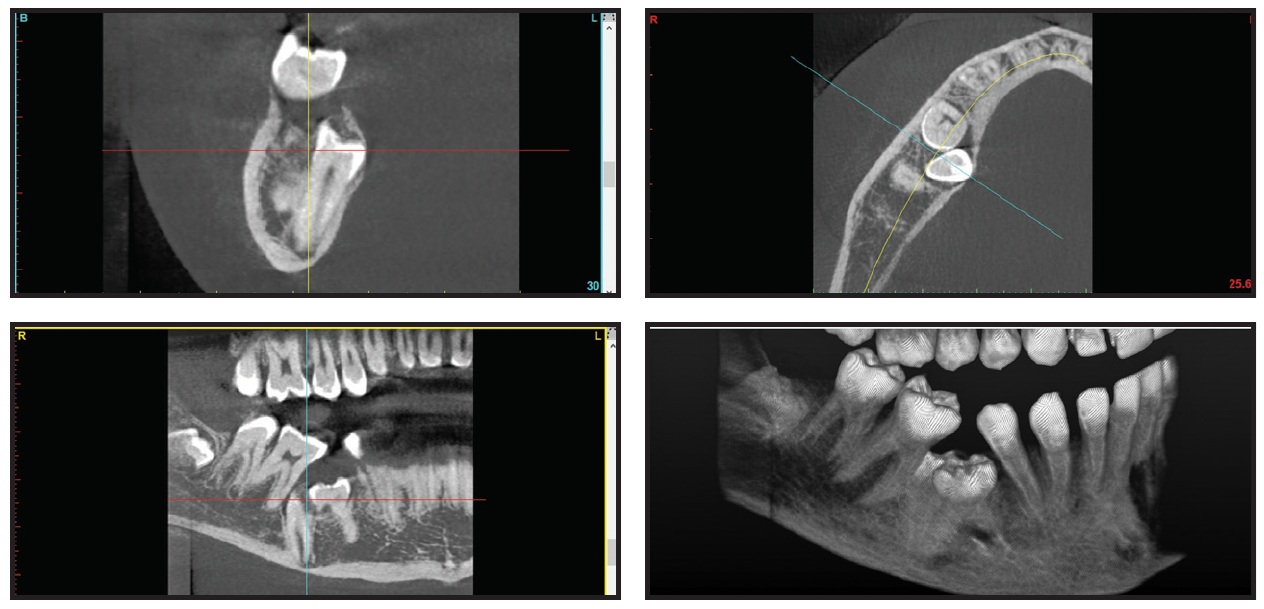

An STL file was automatically converted from the DICOM file using CephX AI algorithms. The segmented model was virtually manipulated for better depiction of the 3D relationships between the objects (Fig. 5). Considering the proximity of the lower right second deciduous molar to the inferior alveolar nerve and the root of the first molar, it was evident that to avoid damaging those structures, the first vector of force on the lower right second premolar should be lingual and mesial. The STL model also demonstrated a severe mesiolingual rotation of the impacted lower right second premolar, which was not apparent in conventional imaging.

Fig. 5 Case 2. A. Pretreatment 3D views from STL files. B. View after virtual extraction of lower right second deciduous molar and section from lower left lateral incisor through lower right first premolar. Note proximity of inferior alveolar nerve (red) to lower right second premolar root (images courtesy of CephX by Orca Dental AI).

The second case demonstrates not only the importance of determining the force application vectors in three dimensions, as previously described,8,22 but also the capacity of AI to readily identify the inferior alveolar nerve—an otherwise arduous manual task for a technician. The ability to manipulate the STL model in all directions and view the relationship between the inferior alveolar nerve and a severely impacted premolar is another major advantage of CBCT in cases of mandibular impactions.23 Because orthodontic forces exerting pressure on the inferior alveolar nerve have been reported to cause temporary paresthesia of the lower lip,24,25 an accurate analysis of the relationship between impacted teeth and the inferior alveolar nerve is particularly important.